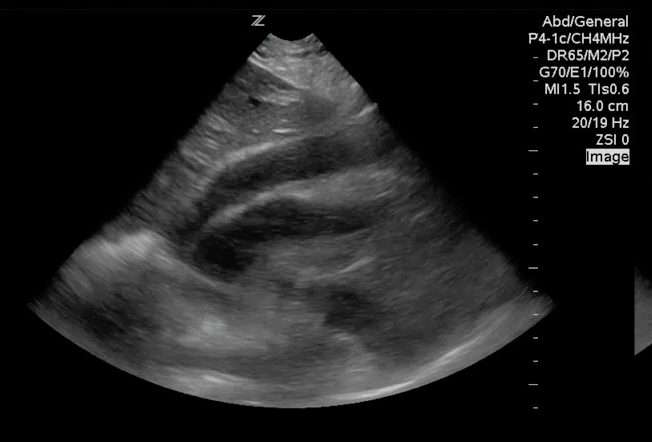

Sonography for Hypotension and Cardiac Arrest Part 1. This + hands on training is how we #meded as we transition students to residents. #POCUS #foamus #foamed